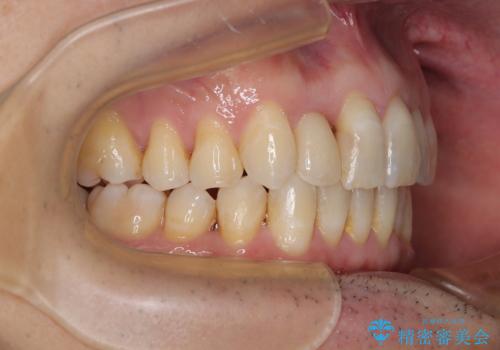

前歯のデコボコを治したい インビザラインによる矯正治療

- 前歯のデコボコを気にして来院された患者様です。

目立たない装置で手軽に治したいとのことで、インビザラインにて矯正治療を行うこととしました。

前歯のクラウンは変色が著しいため、矯正治療後にオールセラミッククラウンにて補綴治療を行うこととしました。

担当医としてはもう少し前歯のデコボコを改善したいところでしたが、患者様としては十分に満足いく歯列であり、マウスピース矯正に飽きてしまったとのことで、治療終了となりました。